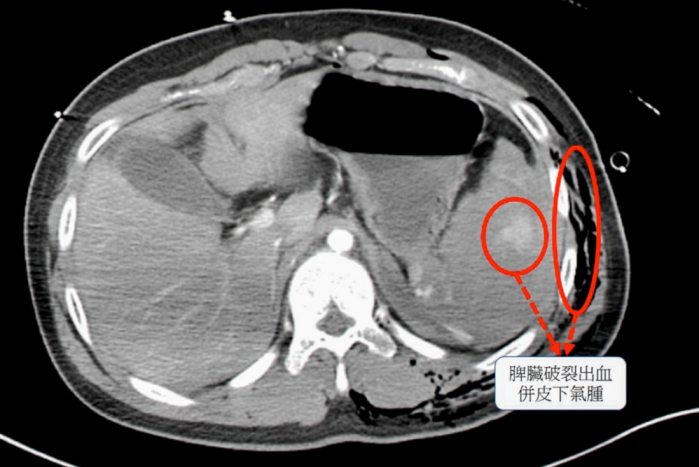

彰基指出,經電腦斷層檢查,確認少年脾臟完全碎裂,為體內大出血主因,同時合併胸腔積血、積氣及多處骨折與血管撕裂傷,面對如此複雜傷勢,外科團隊首先進行緊急手術,切除破裂的脾臟,以控制出血,骨科與整形外科團隊則接力進行骨折固定和血管修補,穩定少年生命跡象。